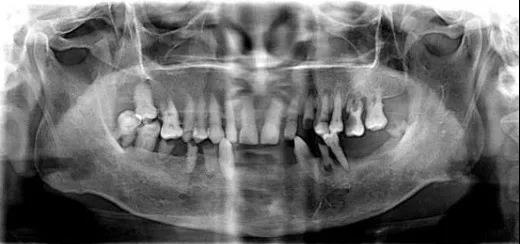

借助德国数字化Sirona CBCT设备,只需要静静地站在设备前等待2分钟左右,就能够迅速获取口内数据,直观了解自己的牙齿内部是否存在问题。

相较于传统的二维X光影像,通过Sirona CBCT重建后我们可以得到三维口内图像。

它的出现彻底改变了传统口腔颌面放射学设备仅能提供二维图像的历史,可以三维显示病变结构,大大提高了诊断能力。

种植医生可以从任意角度观察分析病例,如缺牙区牙槽骨吸收程度、余留牙是否有炎症等需要先进行治疗以避免干扰种植手术的问题。